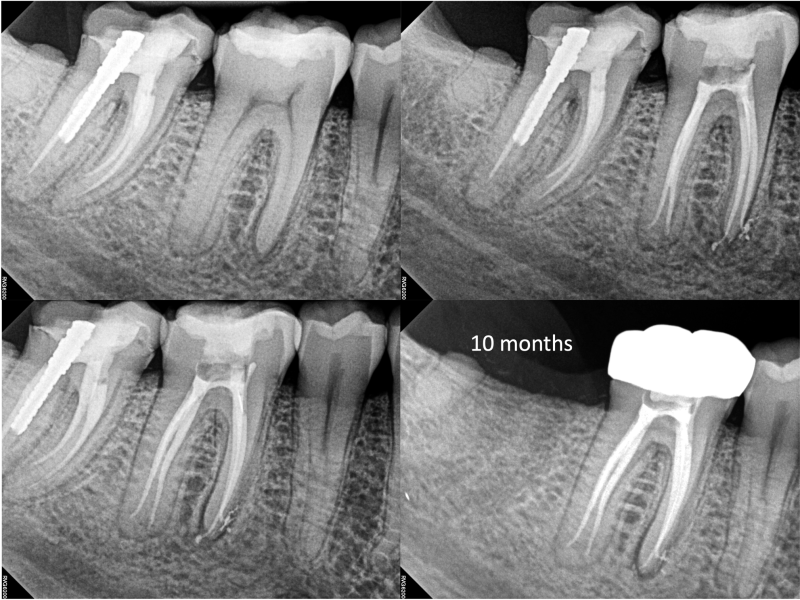

Middle Mesials in MN Molars

Middle Mesials in MN Molars with 10 Months Healing Evidence

Nestor Cohenca, DDS, FIADT

View Case Images